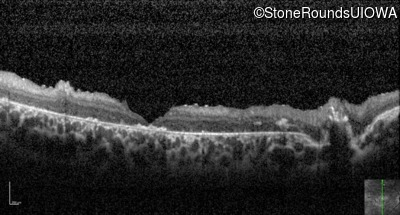

Optical Coherence Tomography - Right - 20/400 sc

Exemplar / OCT Stack